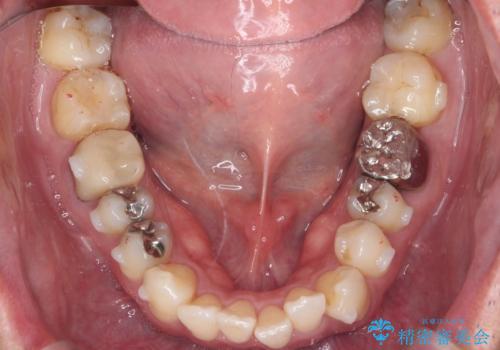

矯正と虫歯のセラミック治療 総合歯科治療の実践

- 突き出た前歯の角度の改善と虫歯治療の改善を求めて来院されました。

虫歯を除去したのち、マウスピース矯正治療を行い、歯並びやがたつきを改善したのち、セラミックに置き換えることで審美性の向上を計画します。

矯正や虫歯治療、セラミック治療といった複合的な治療を一医院で行うことができるのが当法人の大きな特長です。